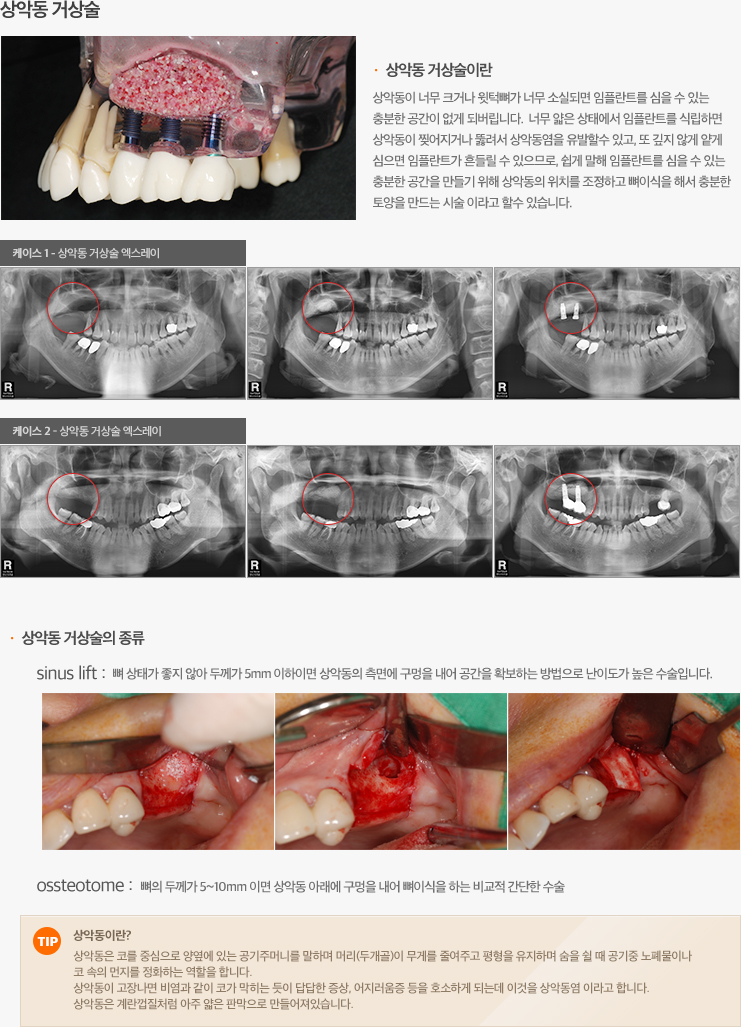

임플란트 이야기 특수임플란트